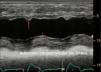

Todas las válvulas protésicas generan un cierto grado de obstrucción comparadas con las nativas, dependiendo del diseño, del tamaño y de la posición anular (intra/supra) de las misma, asemejando una estenosis. Es recomendable consultar los gradientes esperados para el diámetro y modelo de prótesis (Apéndices 1 y 2)31-35. Por ello, puede ser difícil diferenciar la obstrucción hemodinámica de una disfunción leve patológica y del desacoplamiento prótesis-paciente (DPP) o mismatch (tabla 3, fig. 4, Video 4 en material suplementario)36.

En posición aórtica, la morfología triangular del contorno de la velocidad Doppler, con un tiempo de aceleración corto, nos informa de normofunción. Conforme avanza la obstrucción, la morfología de la velocidad Doppler se volverá más redonda, alcanzando el flujo máximo más tardío (fig. 4).

En posición mitral, junto con un gradiente medio elevado, encontraremos un tiempo de hemipresión alargado.

Además de los gradientes valvulares, resulta esencial obtener parámetros flujo-independientes de la función valvular protésica, tales como el área orificial efectiva (AOE) y el índice de velocidad Doppler (IVD) o índice de funcionalismo no dimensional (tabla 3). El valor de IVD obtenido en la fase precoz del postoperatorio puede servir de valor control o «huella valvular» para futuros estudios. Siempre y cuando la función de la prótesis valvular sea normal, el IVD permanecerá constante incluso ante cambios en el volumen sistólico.